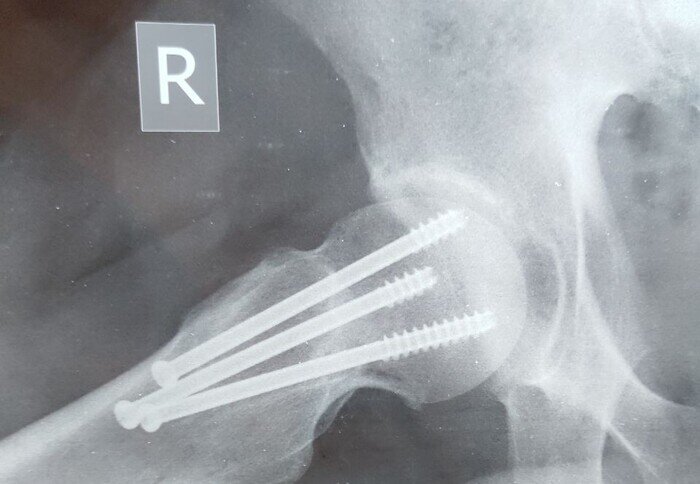

Нога загрустила и поехала в госпиталь снова, где распрощалась с частью себя и обрела замену утраченного. И стала она вот такой: